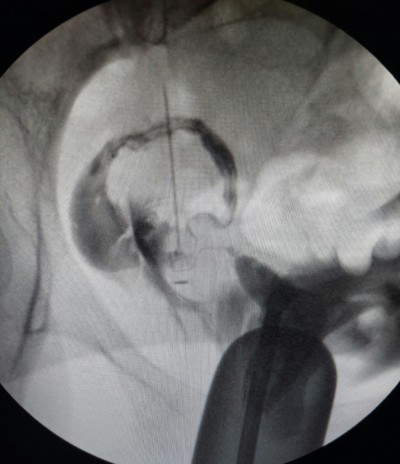

1.5 yıl önce hamile kalmıştım ama 14. Haftada kaybettim. Hsg görüntüsü ekte. Doktor tüpü almaya gerek yok dedi. Bu şekilde bir durum yaşayan, sağlıklı hamile kalan var mı?

Bende de hidrosalpenks vardı. Benimki alındı. Doktorun almaya gerek yok demiş ben başka bir doktora daha gitmeni öneririm. Çünkü diyelim ki açık olan tüpten hamile kaldın. Bebek tutunsa bile içi sıvı dolu tüpten gelen sıvı bebeği zehirleyebilir ya da düşük yapmana sebebiyet verir. Benim tüpüm bu sebeple alındı. Ki Senin de daha önce bir kayıp öykün olmuş.